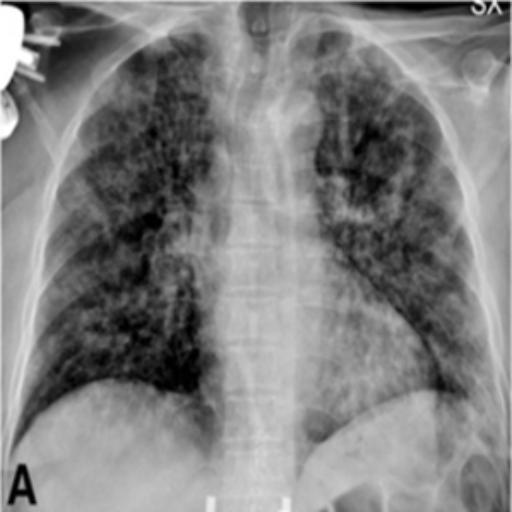

The dataset chosen in this paper is an open-source dataset, the dataset is selected from the open-source database, the database contains 150 lung X-ray images and their corresponding 150 masks, and we select four of them for presentation, the results are shown as follows, the four images in the first row are the original images of the lung X-ray, and the images in the second row in the corresponding position are their corresponding masks, as shown in Fig. 1.

Figure 1. Partial data.